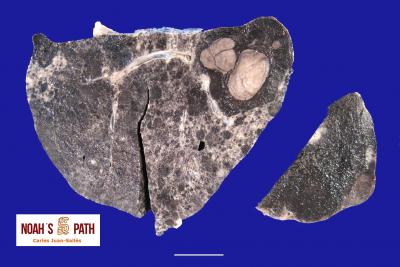

El examen post mortem ofrece una oportunidad única de acceso a todos los tejidos del paciente para diagnóstico de las causas de enfermedad y muerte, y por lo tanto es esencial para medicina preventiva y curativa en grupos de animales, seguimiento de casos, estudios sobre enfermedades, control de zoonosis, medicina de la conservación, y patología forense. En Noah's Path pensamos que un examen post mortem de este tipo de fauna debería ser realizado siempre que sea posible por patólogas/os especializadas/os con el fin de obtener el máximo de información y obtener las muestras más adecuadas.